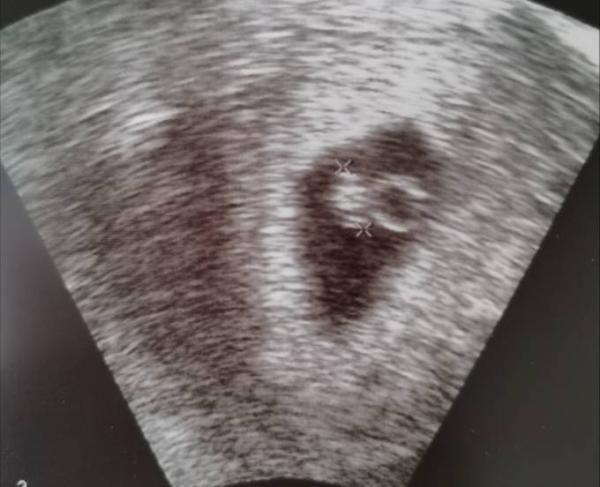

Ich weiss nicht so richtig, ob ich mich freuen kann. Embryo und Herzschlag war da. Da bin ich sehr erleichtert. ABER, ich wurde eine Woche zurückdatiert. Bin 7+5 und der Embryo ist nur 6mm. Also erst 6+4. Das macht mir jetzt wieder große Angst. Nächster Termin ist in 2 Wochen.

Bild zu Zurück vom 1. FA Termin - Forum für Januar - Mamis